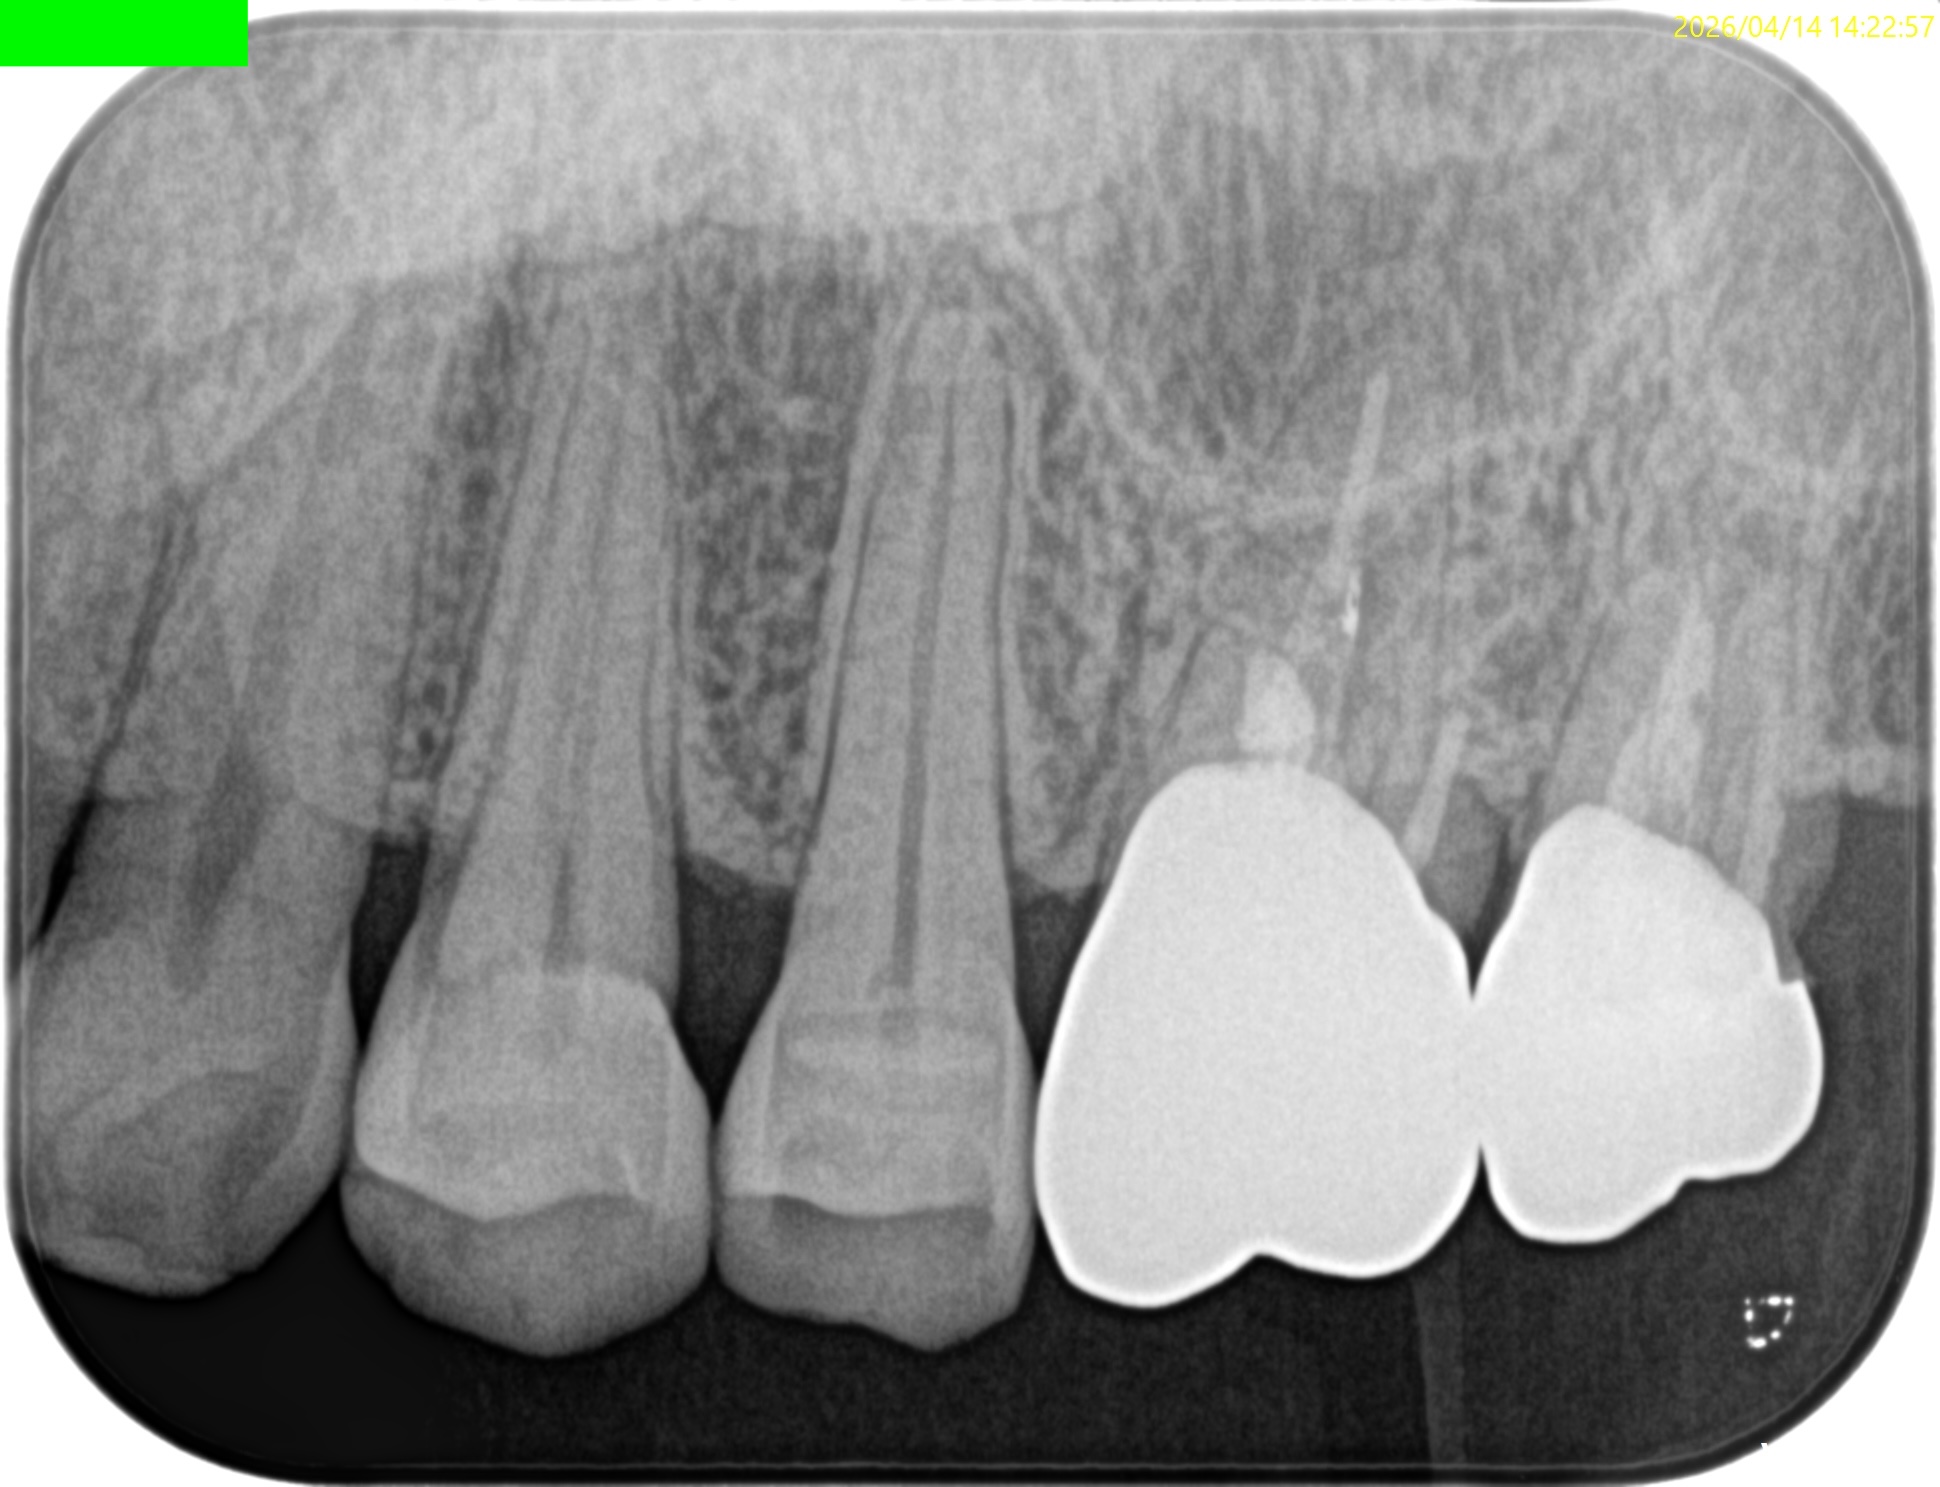

昨日の治療の1年後の予後である。

Retroprepで穿孔させてしまい、即日Retrofill(穿孔封鎖)した#14は治癒しただろうか?

Post-op 1yr recall(2026.4.15)

1年前と比較した。

臨床症状、骨欠損も完治したのでこの日で終診とさせていただいた。